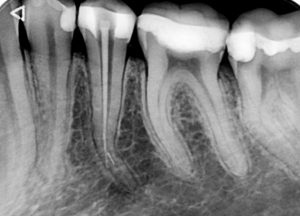

Лечение на гранулом

Случай на случайно открит периодонтит на долен седми зъб. Пациентът дойде при нас, защото “му задържа храна” между два зъба. Рентгенологичната находка ни сблъска с много по-сериозен проблем, лечението на който отне повече от 2 месеца. Седмият зъб бе с диагноза хроничен апикален периодонтит, а грануломът бе обхванал целият зъб, включително и фуркацията на зъба. При шестия зъб положението не беше толкова драматично, но също се наложи да се прелекува, поради същата диагноза като съседния.

Днес, две години след лечението, няма и помен от проблеми и пациентът очаква поставянето на брекетите на долната си челюст.